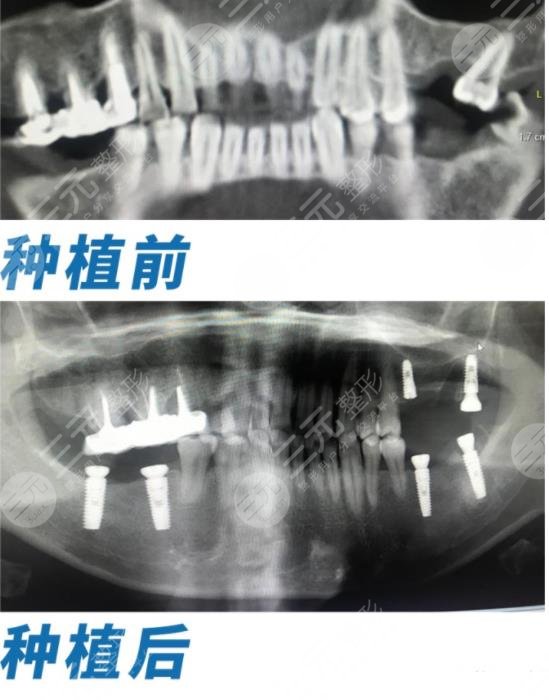

虽然妈妈现在只有55岁,但是因为一些自身原因导致牙齿缺失,很痛苦,每次看到她自己喜欢吃的肉类,都不能去享受,这让我很心疼,为了能让妈妈重新享受口福,我今天带妈妈去种牙,经过许多方面的慎重考虑,我去了深圳正夫口腔医院,在做种植牙之前,老妈还很紧张,但是医院里的医生都很贴心,消除了妈妈的紧张感,记得大概有三个小时吧,全口牙都已经种植完了,果还是很好的。

手术前医生对我进行检查,也确认了我的牙齿不适合填补,只能先把坏死的牙齿拔出后,在植入新的牙齿,这样才不会破坏牙龈,想到要做种植牙,我还是很紧张的,好在医生一直很耐心,为我讲解了很多关于种植牙的注意事项,才让我有勇气选择了全口种植牙手术。